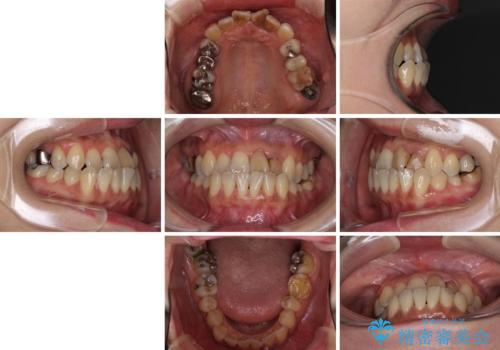

- 前歯の反対咬合により、日々強い痛みを感じているとのことで来院された患者様です。

骨格的に下顎が前方位にありますが、歯列矯正で前歯の被蓋関係を改善することができると判断されたため、インビザラインにより矯正治療を行うこととしました。

また、上顎前歯と下顎大臼歯に神経を取り除いた歯があったため、矯正治療後に、セラミッククラウンにて補綴することとしました。

前歯が内側に倒れ込む力がかかり、正常な歯ぎしりもできないため、非常に負担のかかりやすい咬み合わせでした。

矯正治療中に上顎前歯が下顎前歯を乗り越える際は、前歯でしか咬めない状況が続くため、食事など不便を感じましたが、治療後には前歯の痛みもなくなり、安定した咬み合わせとなりました。